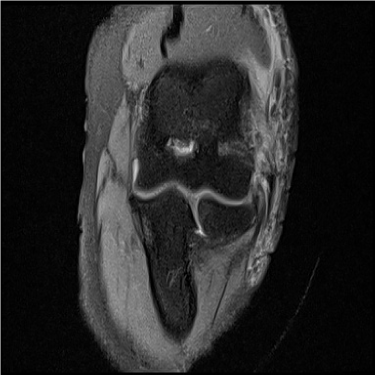

골프엘보 치료 전 MRI

2022.11.16

골프엘보 치료 후 MRI

2022.10.18

테니스엘보 치료 전 MRI

2023.02.17

테니스엘보 치료 후 MRI

2022.07.09

2023.07.16

ㆍ환자 동의를 받은 자료이며, 이미지 사진은 실물과 다를 수 있습니다.

ㆍ모든 자료는 새움병원 자료입니다.